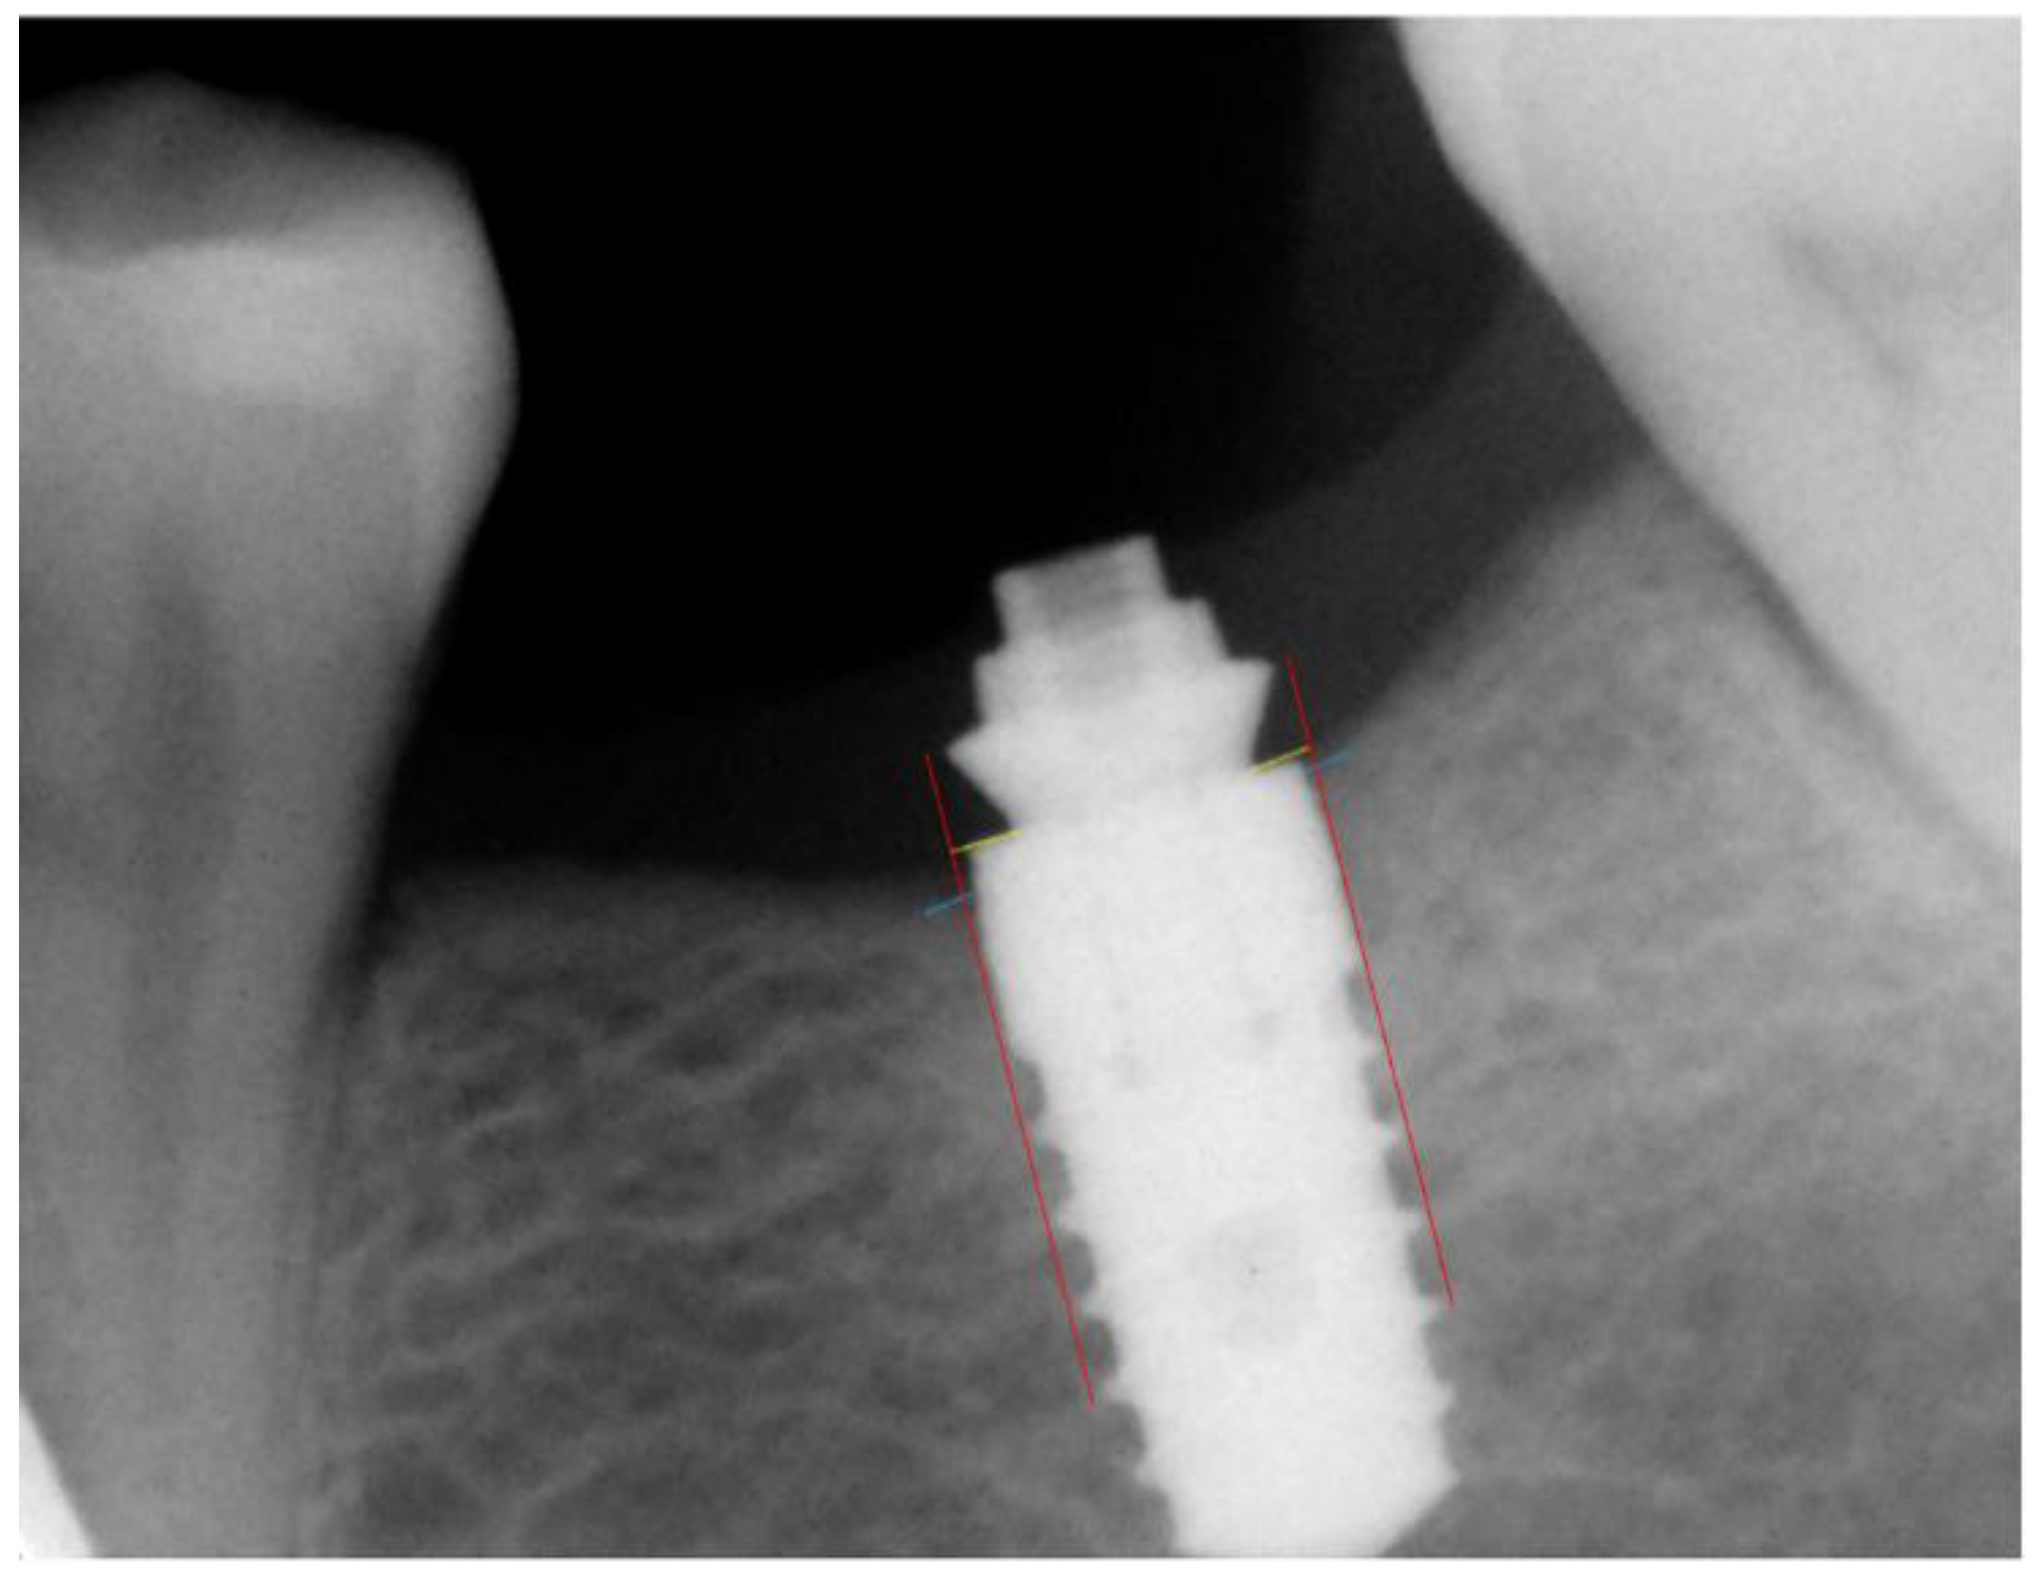

2.8. Radiographic Assessment

| DIB | distance between the implant platform and the first visible bone contact |

- Messias, A.; Tondela, J.P.; Rocha, S.; Reis, R.; Nicolau, P.; Guerra, F. Acrylic Customized X-Ray Positioning Stent for Prospective Bone Level Analysis in Long-Term Clinical Implant Studies. Open J. Radiol. 2013, 03, 136–142. [Google Scholar] [CrossRef] [Green Version]